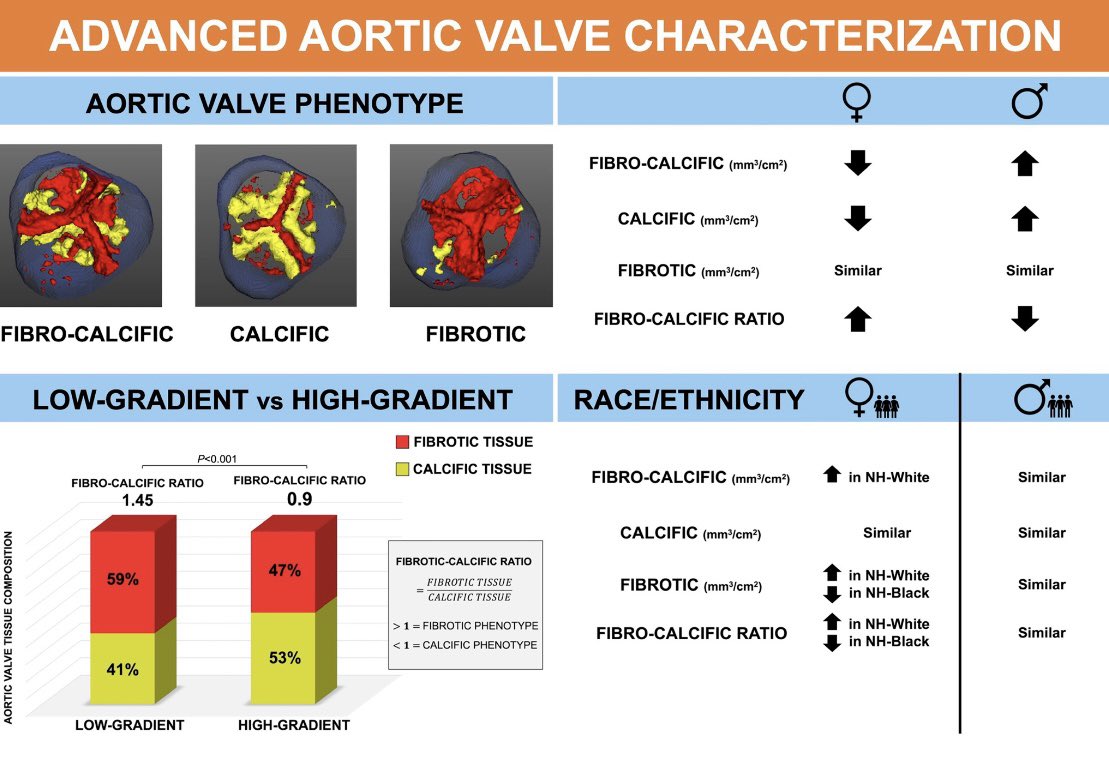

2/ Leandro Slipczuk Pamela Piña S. Aldo L Schenone, MD Carlos Gongora, MD FACC Andrea Scotti Edwin Ho Azeem Latib #AHAJournals Kaz Negishi@Cardiologist/ Heart Mafia ahajournals.org/doi/10.1161/CI…

📣 Check out our latest work on Advanced CT Aortic Valve Characterization just published on CircImaging A wonderful collaboration with Daniel Lorenzatti, MD. and our 💫 Team! Leandro Slipczuk 🔗 ahajournals.org/doi/10.1161/CI… Montefiore Heart Montefiore Health System